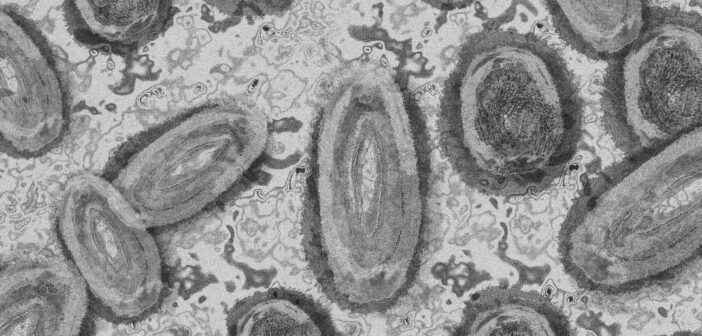

Самое опасное в этой ситуации то, что вирус передается через укусы комаров рода Aedes (в частности, Aedes aegypti и Aedes albopictus). И это не какие-то экзотические насекомые. Эти комары уже давно и прочно обосновались на юге России, особенно на Черноморском побережье и в Краснодарском крае, и с изменением климата их ареал обитания может расширяться на север. Это значит, что теоретически для начала локальной вспышки достаточно, чтобы такой комар укусил зараженного человека, а затем — здорового.